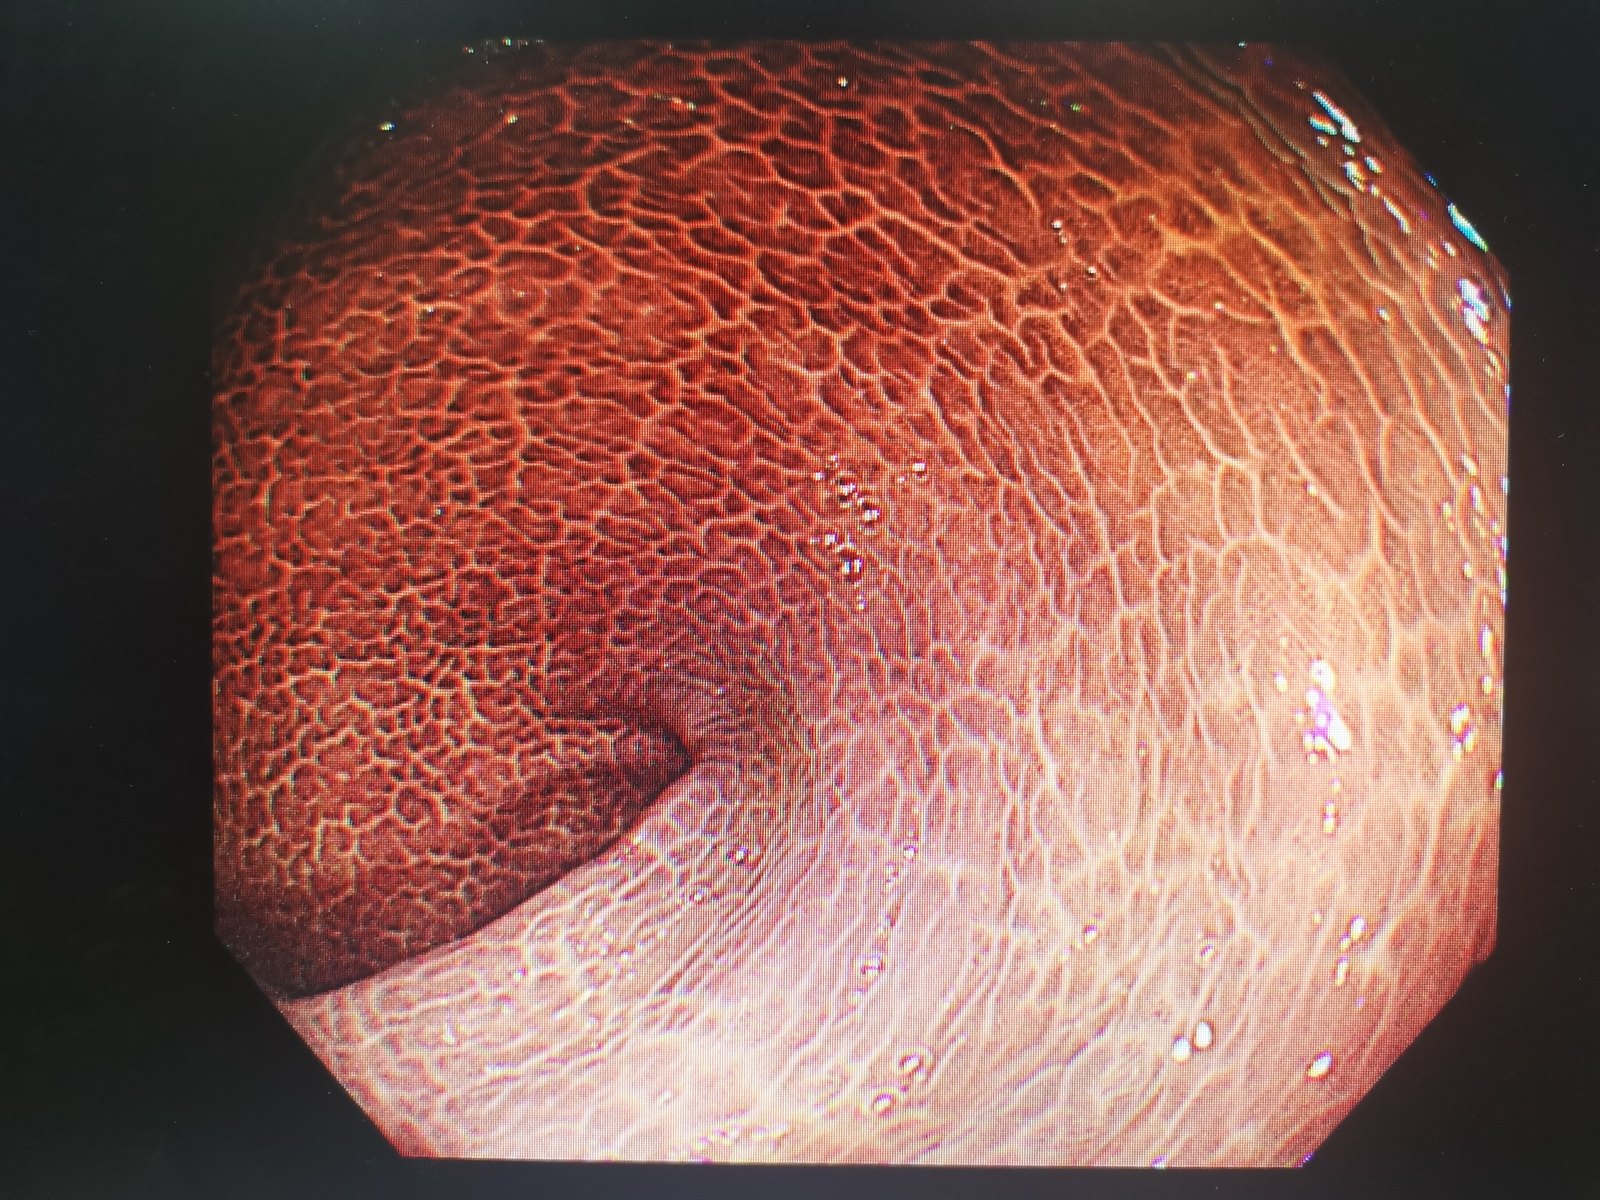

可怕的结肠黑变病_肠疾病_肠疾病相关疾病 - 好大夫在线

图片尺寸1600x1200

清肠茶随便果真的不要随便吃小心结肠黑变病

图片尺寸640x561

什么是结肠黒变病?

图片尺寸1244x1080